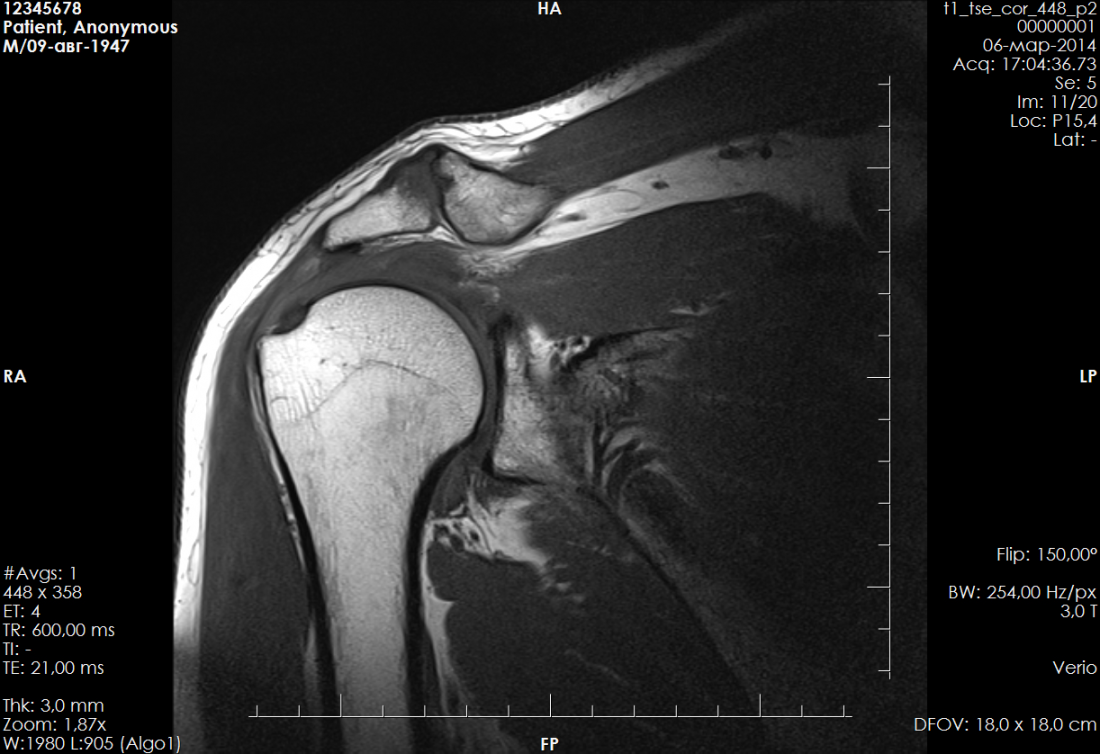

Лучевая диагностика

плечевого сустава

3. Лучевая диагностика патологических изменений сухожилий и мышц ротаторной манжеты

4. Лучевая диагностика повреждений фиброзно -хрящевой губы

5. Лучевая диагностика хондромаляции гленоида и головки плечевой кости

6 Лучевая диагностика патологических изменений структур ротаторного интервала

7. Лучевая диагностика патологических изменений капсулы сустава